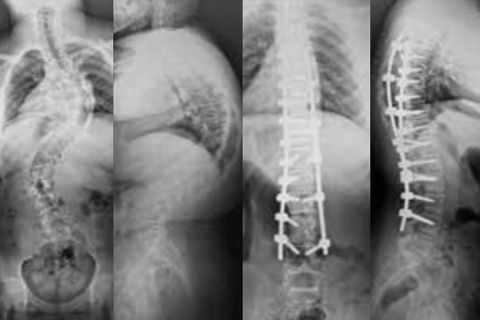

Conferma Sì, sono un operatore sanitario. Cancella No, non sono un operatore sanitario.Caso clinico di Ennovate® in scoliosi idiopatica complessa di un adolescente, eseguito da Bronek Boszczyk e Oded Hershkovich nel Centro medico della Queen, Nottingham, Regno Unito. Il caso è stato presentato durante il Nspine Meeting 2018 in Svizzera e pubblicato anche in Spinal News International a giugno 2018.